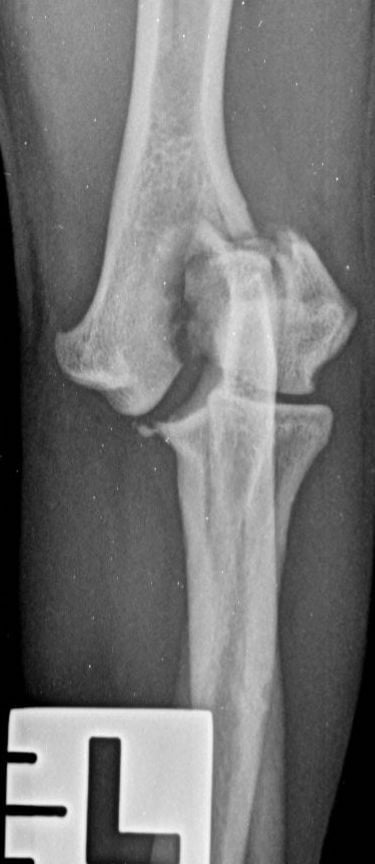

Traditionally, humeral unicondylar (lateral or medial) fractures have been managed with internal fixation using a transcondylar bone screw and an anti-rotational device. This is generally a Kirschner wire (K-wire) or Steinmann pin (Figure 1), which is placed across the epicondylar ridge component of the fracture (Bojrab, 1975; Denny and Butterworth, 2000; Jackson, 1983; Olmstead, 1993). However, reports of complications relating to mechanical failure due to implant migration in a series of patients varying widely in age and breed concluded that using a supracondylar K-wire is more likely to cause major complications than using an epicondylar bone plate (Perry et al., 2015; Sanchez Villamil et al., 2019). This conclusion was endorsed by an in vitro study that showed that stiffness, yield load and load to failure are all greater when bone plates, rather than K-wires, are used in conjunction with a transcondylar bone screw to stabilise humeral unicondylar fractures (Coggleshall et al., 2017).

These concerns have led to recommendations being altered over the past decade or so, with veterinarians now using bone plates, instead of K-wires, as an adjunct to a transcondylar screw when managing humeral unicondylar fractures (Figure 2), even in puppies (Figure 3) (Clark, 2016; Kvale et al., 2022). However, the basis on which this conclusion for puppies was reached appears to have been flawed because it assumed that what had been shown to be the case for adults would also apply to immature patients. As the conclusion was felt to conflict with the author’s experience of treating such patients, a retrospective study was undertaken to evaluate complications and outcomes in immature dogs treated for humeral unicondylar fractures at one centre over a 10-year period (Butterworth, 2022). The findings of this study are summarised in this article.